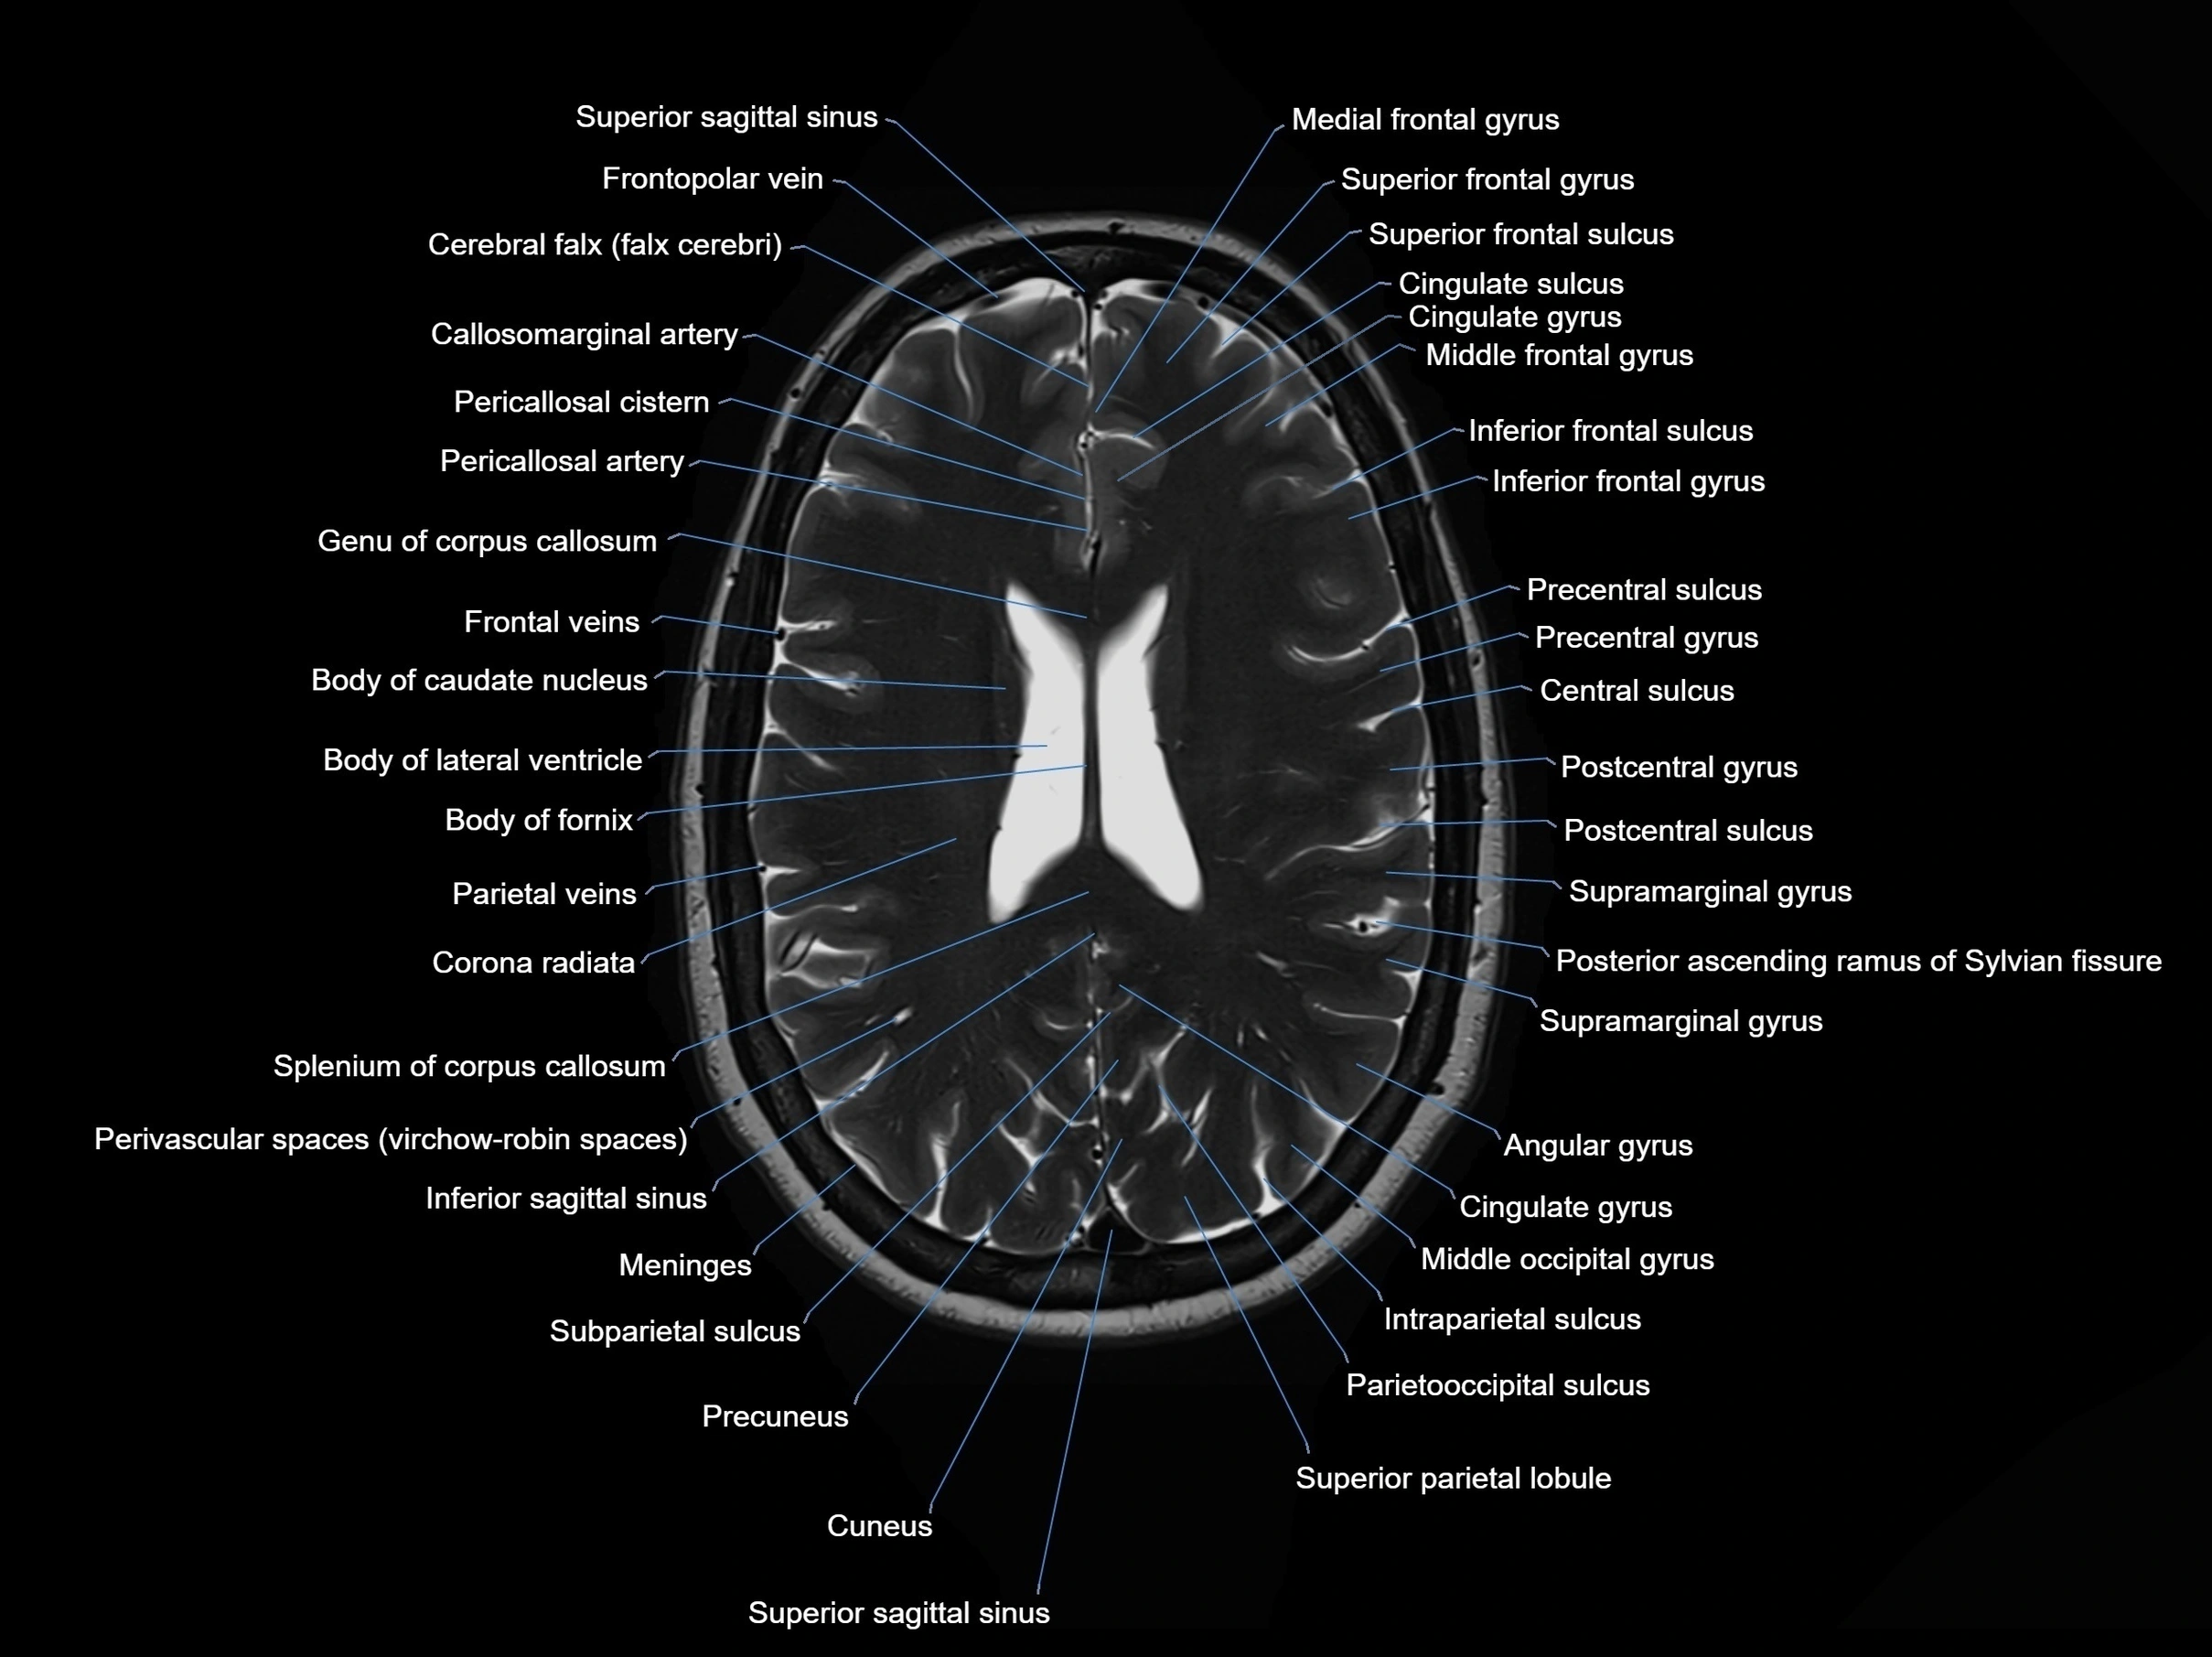

MRI images